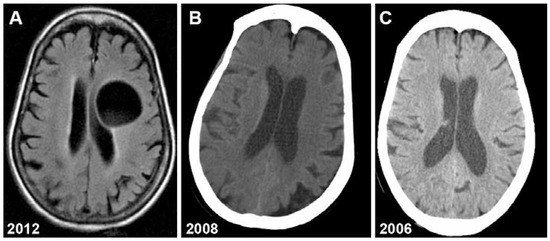

Primary Cerebral Echinococcosis Presenting as Long-Standing Generalized Weakness

by Jennifer Madeo, Xi Zheng, Shadab Ahmed and Radhames Ramos De Oleo

Echinococcosis is an infectious disease that can remain dormant for years. The most common sites of infection are liver and lungs. Primary cerebral disease is very rare. Here we report on an unusual case of echinococcosis, where the only identifiable lesion was a [...] Read more.

Echinococcosis is an infectious disease that can remain dormant for years. The most common sites of infection are liver and lungs. Primary cerebral disease is very rare. Here we report on an unusual case of echinococcosis, where the only identifiable lesion was a slowly growing intracranial hydatid cyst. No lesions on the liver identified. The patient is a United States immigrant from rural South India with a chief complaint of progressive weakness and aphasia. Further analysis revealed an interesting association between the clinical, anatomical and hematological findings over time. We conclude that hydatid cyst disease should be considered in patients from endemic areas with long-standing neurological symptoms. Full article

Show Figures

Figure 1